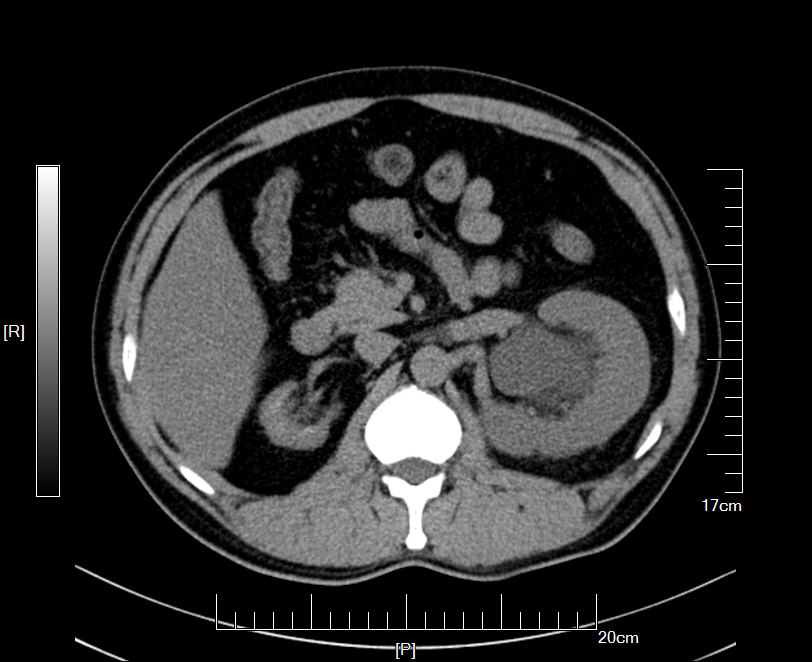

CT检查提示:右肾萎缩无功能,左侧肾脏代偿性增大,左肾积水扩张,双侧输尿管结石

2016年09月手术患者,男性,83岁,太仓人,双侧腰酸不适五年伴体检发现双侧输尿管结石一周入院,五年来患者自觉双侧腰酸,一直未予重视,近期自觉双下肢浮肿且左侧腰痛明显加剧,遂参加社区免费体检时发现双侧输尿管结石遂来院就诊,CT:右肾萎缩无功能,左侧肾脏代偿性增大,左肾积水扩张,双侧输尿管结石,左侧约1.5cm,右侧约2.0cm GFR:左侧41.27ml/min,右侧5.2ml/min。肾功能:Cr 571umol/L;术前诊断:双侧输尿管结石 右肾萎缩 右肾无功能 左肾积水,鉴于右输尿管结石梗阻时间太长,右肾已几乎无功能,萎缩固缩,且肾功能已失代偿,遂只能急症先输尿管镜处理左输尿管结石,保护左侧肾脏,待肾功能稳定后再处理右侧输尿管结石及右肾,患者预后不容乐观。